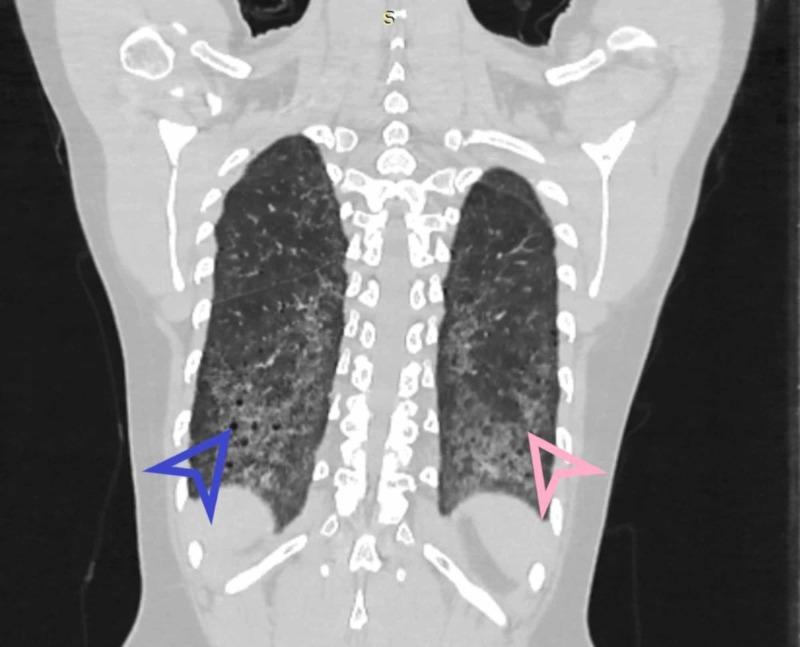

类风湿关节炎相关间质性肺疾病:高分辨率计算机断层扫描模式

Rheumatoid Arthritis Related Interstitial Lung Disease: Patterns of High-resolution Computed Tomography.

Background and aim Rheumatoid arthritis (RA) is a chronic inflammatory systemic disease characterized by bilateral involvement of mostly small joints of hands and feet. There can be various extra-articular manifestations of the disease including lung parenchymal disease. Pulmonary involvement in RA patients leads to increased morbidity and mortality. The overall burden of RA related pulmonary disease is underestimated due to the limitation of resources in underdeveloped countries. High-resolution computed tomography (HRCT) is an important tool used to diagnose different abnormalities in RA related interstitial lung disease (ILD). The objective of the study was to evaluate HRCT findings in patients of RA related ILD and categorize the radiological findings according to clinical findings. Method This descriptive prospective observational study was conducted at Mayo Hospital, Lahore from June 2014 to June 2015. Patients of RA suspected of lung disease after selection underwent HRCT chest on 128-slice Hitachi CT scanner (Hitachi Global, Tokyo, Japan) in the radiology department. Images were reconstructed and evaluated by experienced radiologists. Findings were recorded on a questionnaire. Data was analyzed on SPSS version 21 (IBM Corp, Armonk, US). Results Out of the 54 patients scanned, interlobular septal thickening was the most common finding found in 22 of the patients. Ground-glass opacification was recognized in 21 patients, honeycombing in nine and bronchiectasis in two patients. Regarding zonal predilection of disease pattern, lower zones of lungs were found involved in most of the cases. The disease was found to be bilateral in 15 patients. Based on these findings, usual interstitial pneumonitis (UIP) was diagnosed in six patients and non-specific interstitial pneumonitis (NSIP) in 14 others. Conclusion This study concluded that HRCT images are very useful in diagnosing interstitial lung disease related to rheumatoid arthritis.

摘要